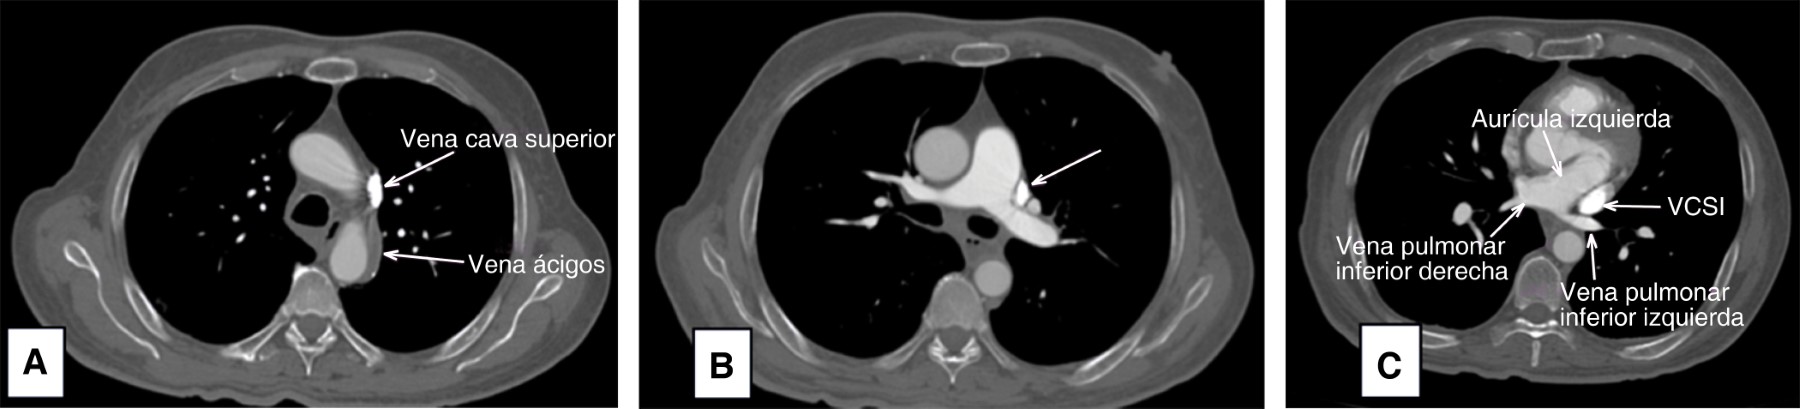

Pacemaker implantation through the persistent left superior vena cava due to the absence of the right superior vena cava. Report of a case

Introduction: the persistence of the left superior vena cava (PLSVC) has a prevalence of 0.21% in the general population. Case presentation: 67-year-old male diagnosed with third-degree AV block, requiring pacemaker placement. However, due to the absence of a right superior vena cava, corroborated by CT angiography, a definitive pacemaker was placed through a persistent left superior vena cava. Conclusion: the persistence of the left superior vena cava (PLSVC) is the most common thoracic venous anomaly. It can cause a number of clinically significant symptoms, even in a heart with normal anatomy. Pacemaker placement makes electrode fixation difficult due to tortuous travel.

Figure 3